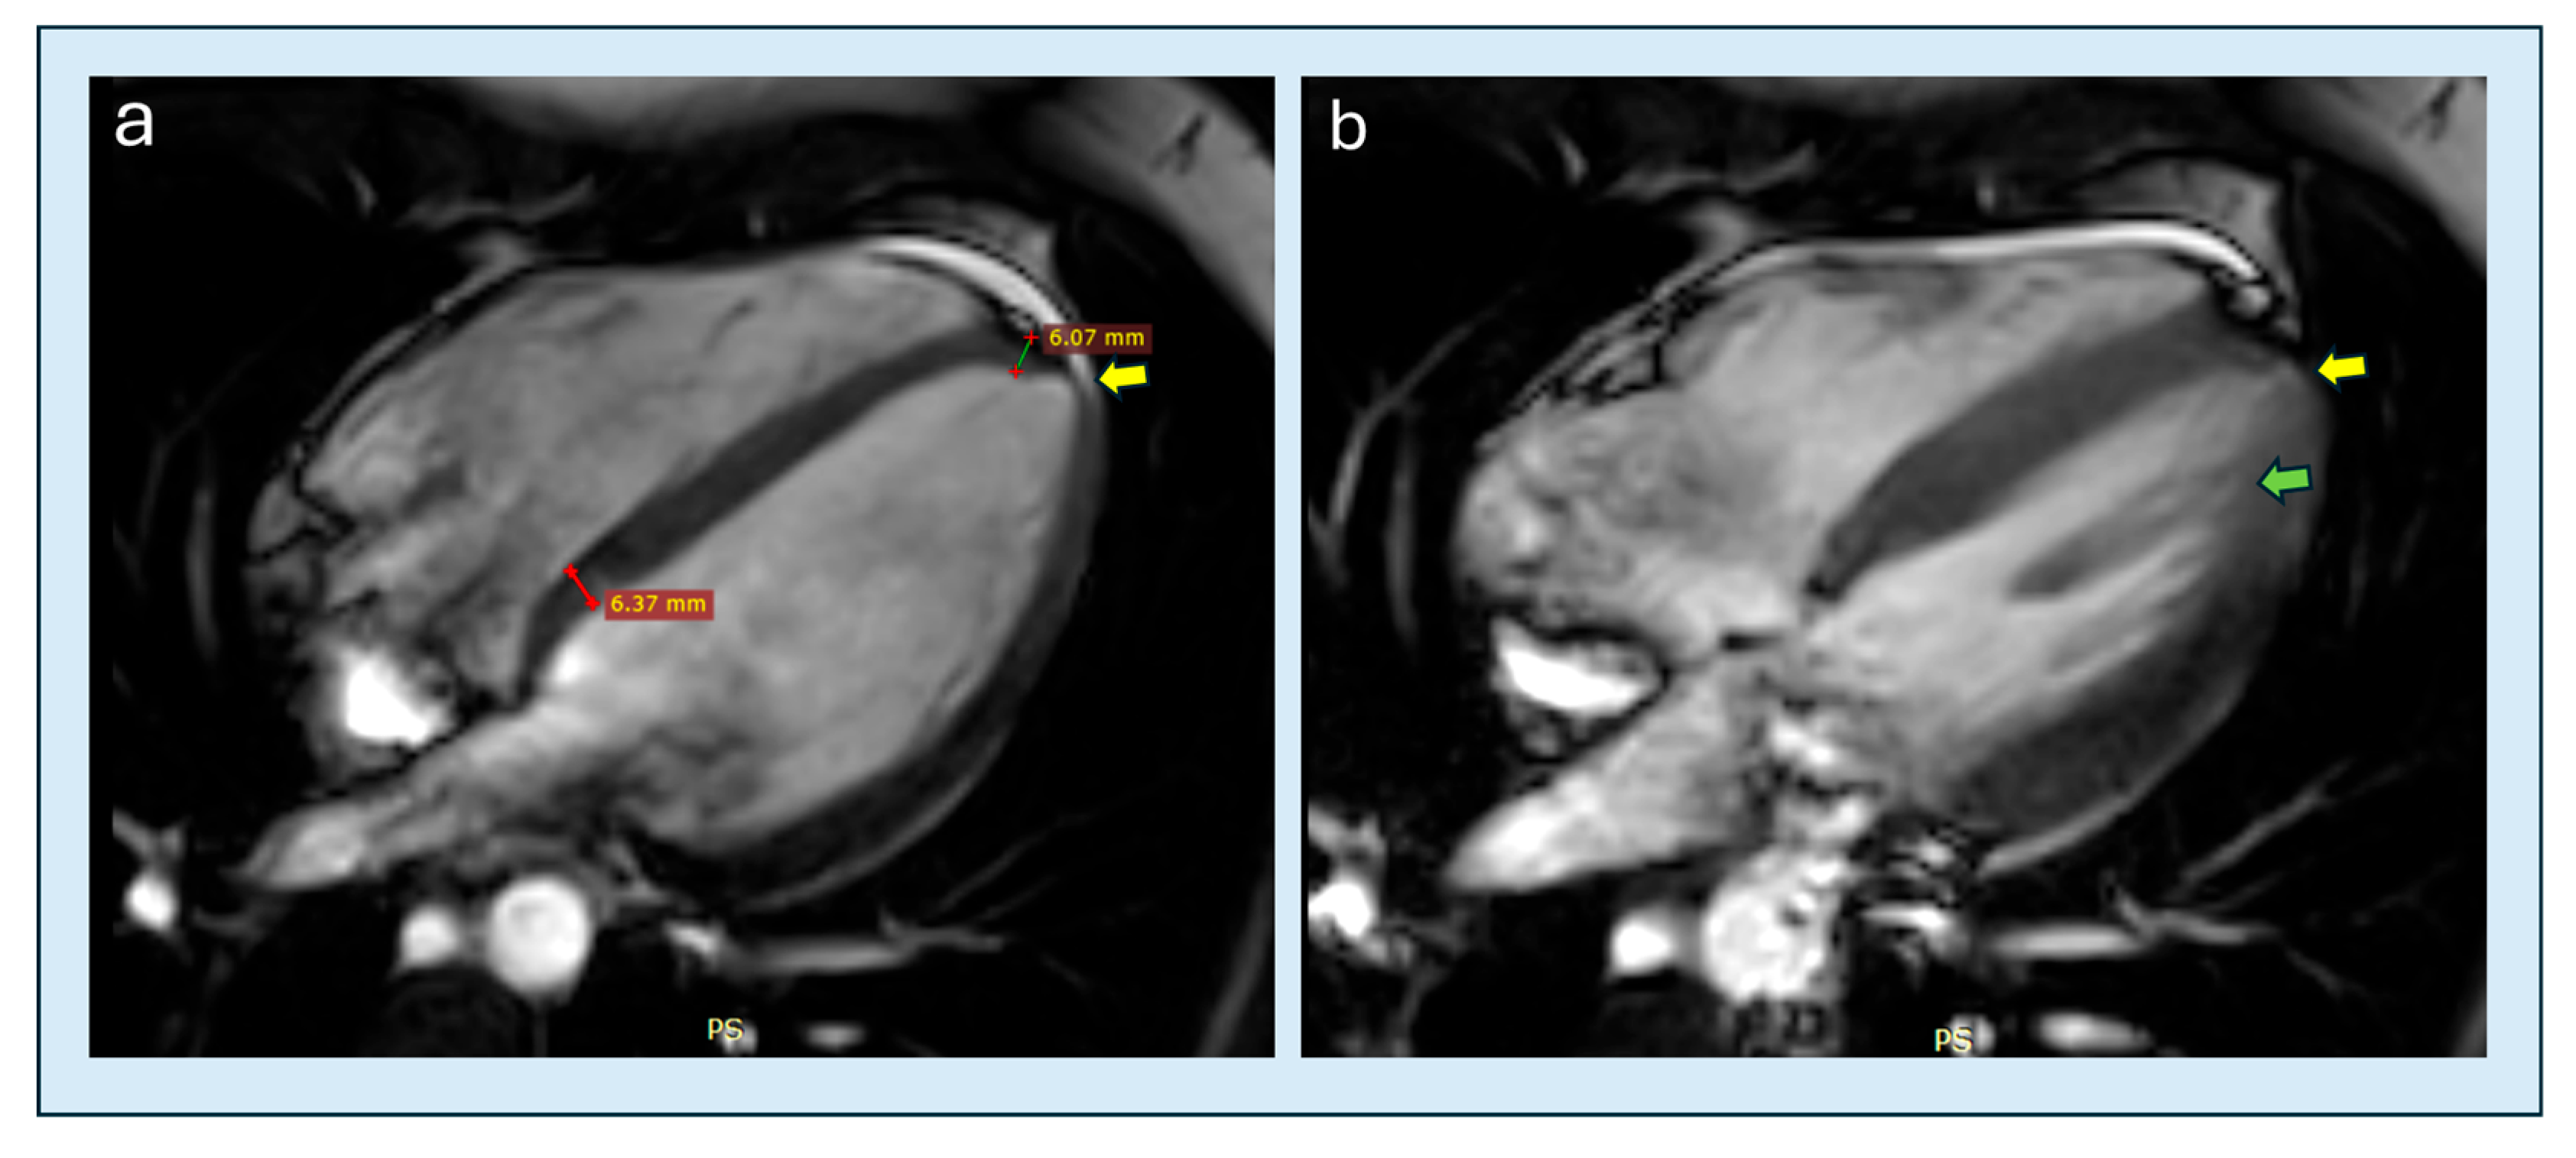

- Filomena, D.; Vandenberk, B.; Dresselaers, T.; Willems, R.; Van Cleemput, J.; Olivotto, I.; Robyns, T.; Bogaert, J. Apical papillary muscle displacement is a prevalent feature and a phenotypic precursor of apical hypertrophic cardiomyopathy. Eur. Heart J. Cardiovasc. Imaging 2023, 24, 1009–1016. [Google Scholar] [CrossRef]

| Apical papillary displacement | CMRi | Apical beyond mid-LV | >150 HCM + ctrls | Supportive | Moderate | + | Filomena 2023 [76] |